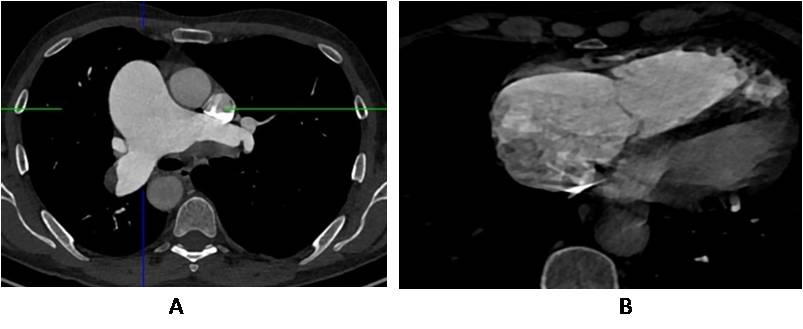

According to the control multispiral СT–angiopulmonography, performed on the 8th day after thrombolytic therapy, there was a negative trend in the form of total occlusion of the segmental branches of the right pulmonary artery (PA), an increase in the obstruction area of the lower lobar branch of the left РА up to 68%, as well as signs of a sharp overload of the right heart chambers (Figure 2). In the objective status, there was a progressive deterioration of the condition in the form of an increase in shortness of breath, a drop in the parameters of central hemodynamics. 5 September 2021 the patient was examined by a cardiovascular surgeon of the clinic through the aviation ambulance, as a result of which an open surgical intervention was indicated — thromboembolectomy (TEE) from the PA in a specialized cardiosurgical hospital.

Fig. 2. Fragments of multispiral computed tomography — angiopulmonography angiopulmonography in axial planes. Signs of a sharp overload of the right chambers of the heart: — balloon-like dilatation of the trunk and main branches of the pulmonary artery (2A); a sharp increase in the size of the right chambers of the heart, the ratio of the transverse size of the right ventricle in relation to the left as 1.8:1.0; dilatation of the right atrium (2B).